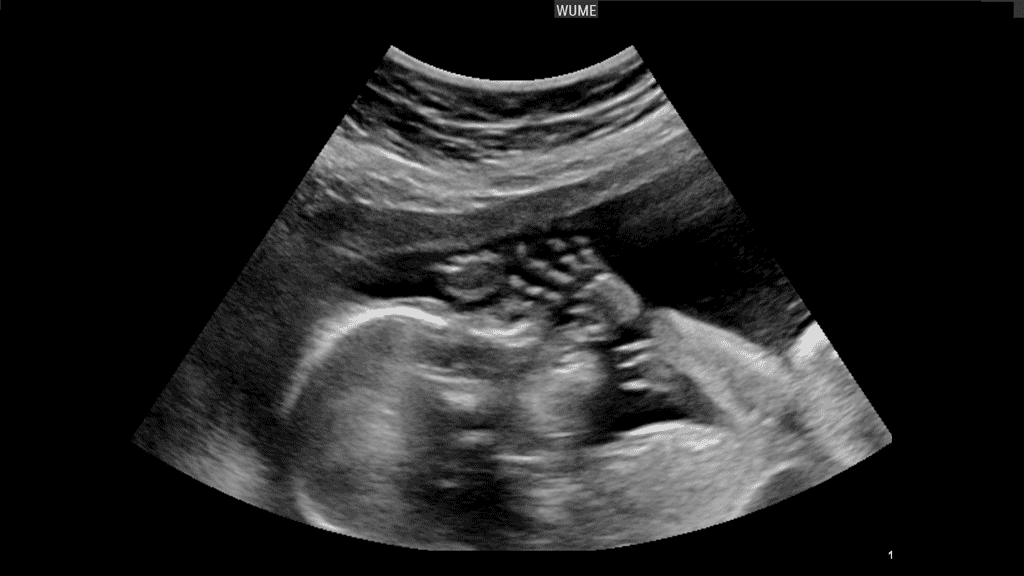

سونوگرافی غربالگری سه ماهه اول بارداری؛غربالگری سه ماهه اول

اگرچه اکثریت قریب به اتفاق زنان باردار نوزاد سالمی دارند، اما در مواقعی این اتفاق نمی افتد. غربالگری سه ماهه اول یک آزمایش سونوگرافی و بیوشیمیایی است که اساساً برای ارزیابی احتمال فردی بارداری شما برای مشکلات کروموزومی جنین طراحی شده است.

سونوگرافی برای ارزیابی اندازه جنین، با اندازهگیری طول آن از سر تا پایین (Crown Rump Length) استفاده میشود.

علاوه بر این، شفافیت نوکال، که یک فضای خالی اکو کوچک در پشت گردن جنین است، اندازه گیری می شود. همه جنینها شفافیت نوکال دارند، اما هرچه اندازهگیری شفافیت نوکال بزرگتر باشد، احتمال بروز مشکل در نوزاد (مثلاً سندرم داون یا نقص ساختاری قلب) بیشتر میشود.

سونوگرافی تصاویری از نوزاد ایجاد می کند . سونوگرافی برای غربالگری سه ماهه اول به دنبال مایع اضافی در پشت گردن نوزاد است . اگر در سونوگرافی مایع افزایش یافته باشد ، ممکن است اختلال کروموزومی یا نقص قلبی در نوزاد وجود داشته باشد.

سونوگرافی NT (Nuchal Translucency): در این سونوگرافی، ضخامت مایع پشت گردن در جنین اندازهگیری خواهد شد. افزایش ضخامت این ناحیه میتواند نشانهای از برخی ناهنجاریها باشد.